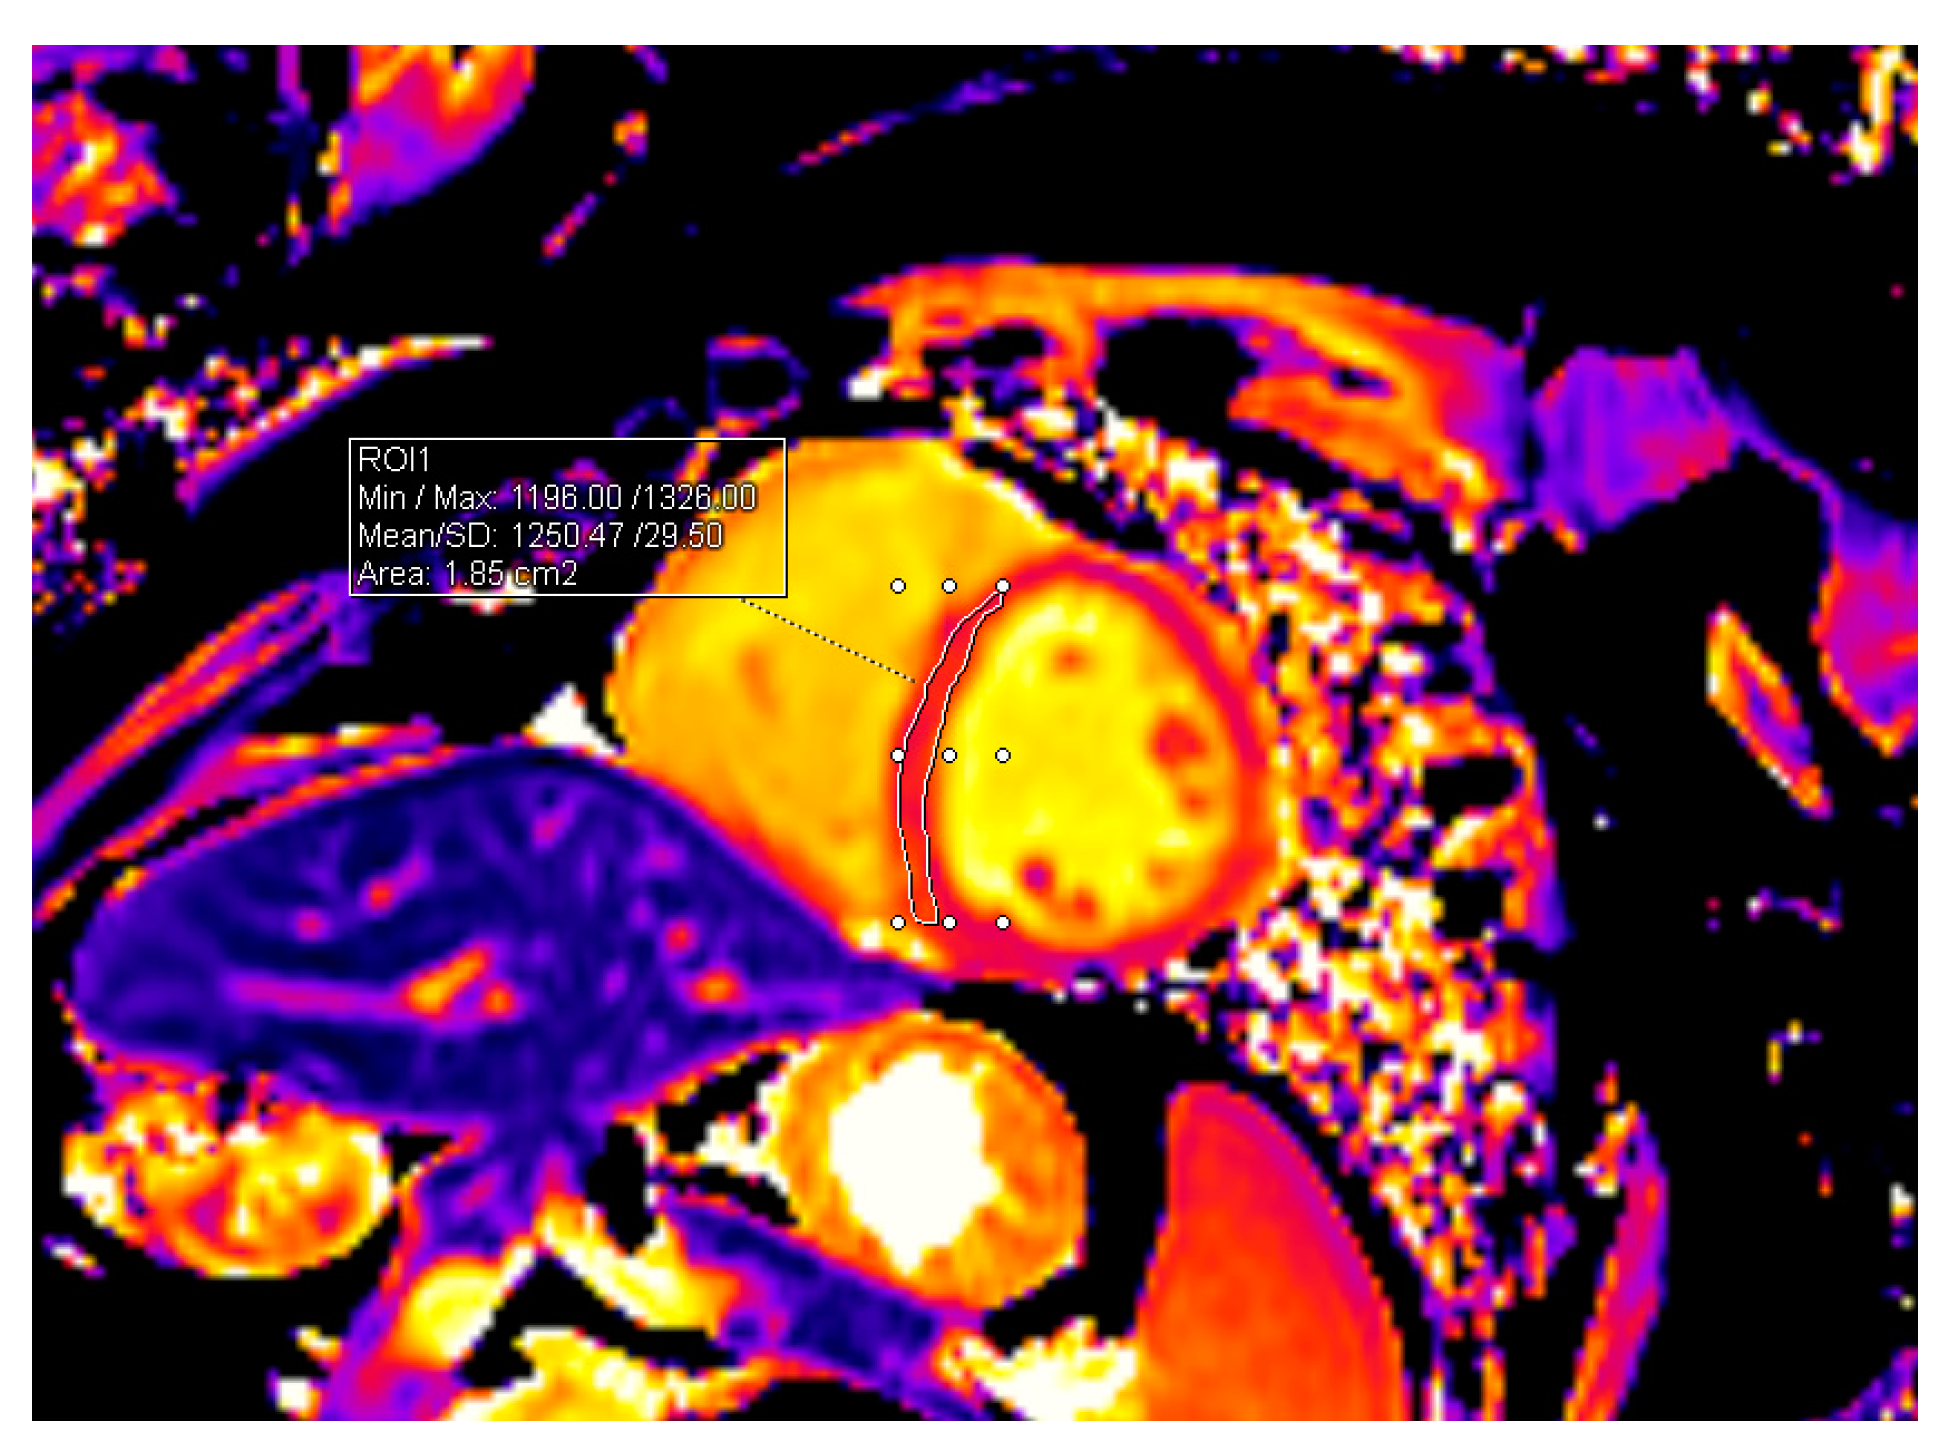

| T1 mapping value, ms | 1226.13 ± 39.74 | 1248.70 ± 41.07 | 0.010 |